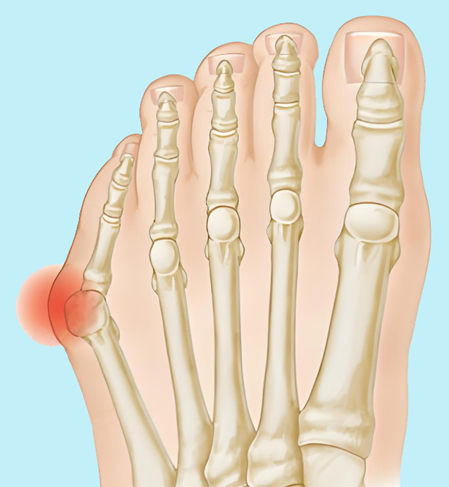

(一)拇囊炎

拇囊炎是造成足部疼痛常见原因之一,是指足部第一跖趾关节的关节囊出现炎症,表现出疼痛、发红及肿胀的症状群,是遗传及其他因素综合所导致,常合并第一跖趾关节炎。

图3:拇囊炎

▶穿紧身不合脚的鞋子,尤其是高跟鞋和尖头鞋,会增加拇囊炎的风险。女性的发病率是男性的10倍。

▶拇囊炎单独发生的几率并不高,是拇外翻患者最容易出现的症状,但并不是所有的拇外翻畸形都伴有该症状。

▶对于症状较轻的拇囊炎,保守治疗具有较好的效果,包括穿宽松舒适的鞋子、穿戴拇囊炎垫和局部物理治疗。

▶对于畸形较重的拇囊炎患者,需手术治疗。一般以矫正拇外翻畸形为首要目标,对畸形的骨性结构进行三维矫正,同时去除增生骨突以及炎性增生的滑膜,从根本上纠正畸形,去除拇囊炎的病因。